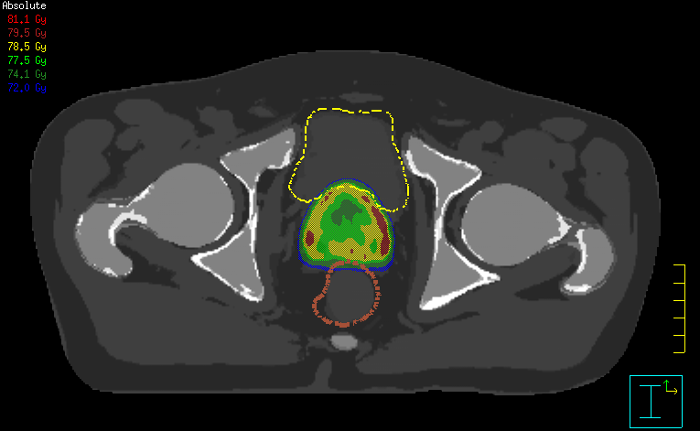

The ability to tune contrasts can provide even more valuable information about tumor characteristics and tumor extent to facilitate enhanced delineation, and also provides possibilities for dose boosting strategies.

Innovative strategies in MRI-only simulation have made it possible to derive CT-like electron density information from MR imaging data. This capability enables physicians to use MRI as the radiotherapy department’s primary imaging modality for specific applications to eliminate tedious and error-prone CT-MR registration and simplify workflows.